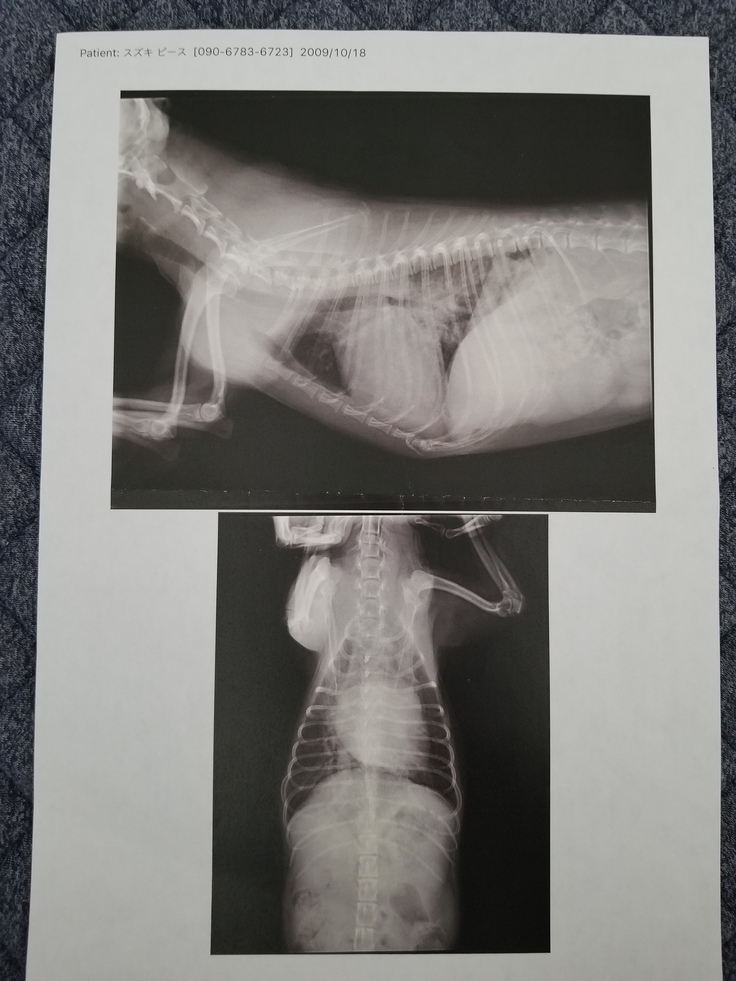

この病気は進行性の病気で、僧帽弁を支える腱索(組織)が断裂すると血液の逆流量も増え、心臓が肥大、逃げ場を失った血液は肺に流れ、血液中の水分が肺に溜まってしまう症状が「肺水腫」です。「肺水腫」はレントゲンを撮ると肺の周りが白く映り、下記の画像は正にその状態です。

本来、僧帽弁閉鎖不全症の診断は心音に雑音が生じていると判別できるものです。ピースは定期的に通院しており、その度に心音や呼吸の音を確認してもらっていましたが、その際には異常は見つかりませんでした。徐々に進行していて突然、症状が目に見える様に発症したのだと思われます。